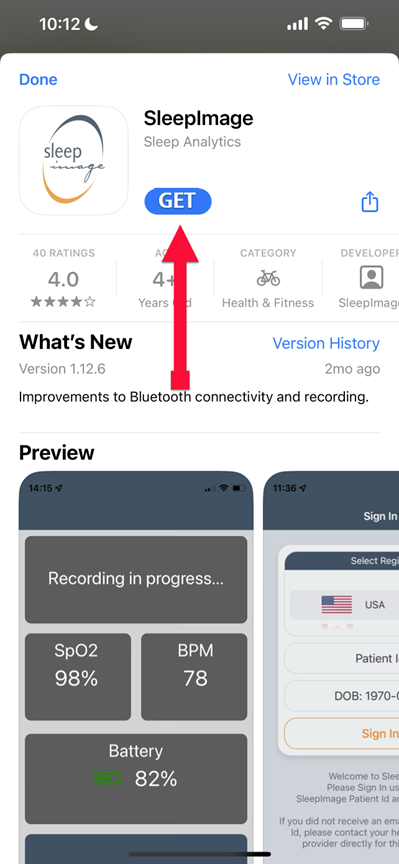

SLEEPIMAGE APP (iPhone)

SLEEPIMAGE APP (iPhone)

SLEEPIMAGE APP (iPhone)

SLEEPIMAGE APP (iPhone)

SLEEPIMAGE APP (iPhone)

SLEEPIMAGE APP (iPhone)

SLEEPIMAGE APP (iPhone)

SLEEPIMAGE APP (iPhone)

SLEEPIMAGE APP (iPhone)

SLEEPIMAGE APP (iPhone)

SLEEPIMAGE APP (iPhone)

SLEEPIMAGE APP (iPhone)

SLEEPIMAGE APP (iPhone)

SLEEPIMAGE APP (iPhone)

SLEEPIMAGE APP (iPhone)

SLEEPIMAGE APP (iPhone)

SLEEPIMAGE APP (iPhone)

SLEEPIMAGE APP (iPhone)

SLEEPIMAGE APP (iPhone)

SLEEPIMAGE APP (iPhone)

SLEEPIMAGE APP (iPhone)

SLEEPIMAGE APP (iPhone)

SLEEPIMAGE APP (iPhone)

SLEEPIMAGE APP (iPhone)

SLEEPIMAGE APP (iPhone)

SLEEPIMAGE APP (iPhone)